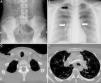

Respuesta de los autores al artículo «Migración intratorácica de catéter de derivación ventriculoperitoneal: a propósito de un caso» por Y. Sánchez-Medina et al.

Author's response to article «Intrathoracic migration of a ventriculoperitoneal shunt catheter: A case report» by Y. Sánchez-Medina et al.